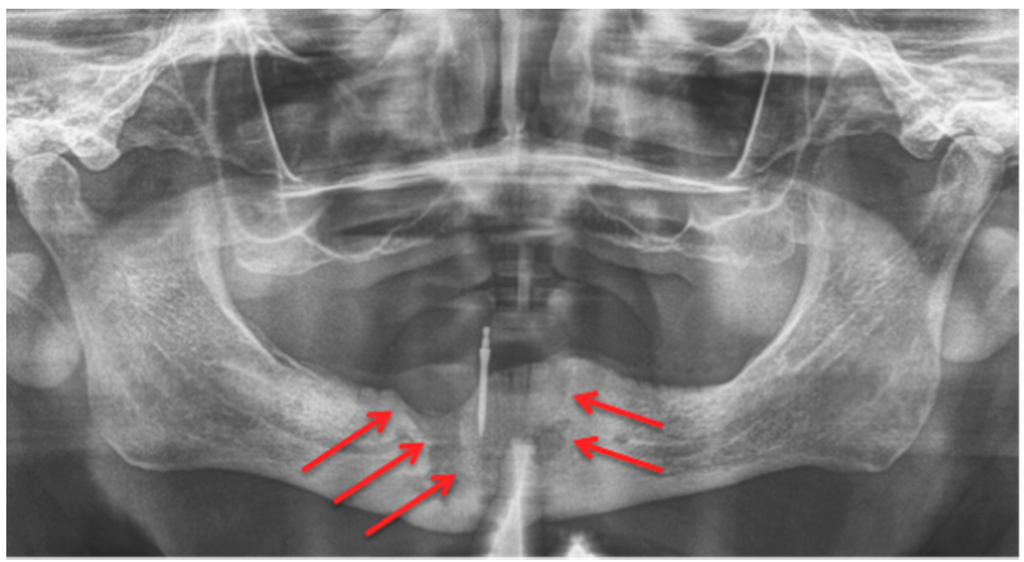

In a daily routine, a clinical examination and a radiograph are the minimum examinations required in order to detect lesions and to provide data for a follow-up appointment. For Marx et al., panoramic imaging is the image of choice for a routine dental assessment in these patients [13]. Figure 1, Figure 2 and Figure 3 exemplarily depict typical findings of panoramic radiographs.

Figure 1.

Panoramic radiograph: Patient: 48 years old, female, metastatic breast cancer, zoledronic acid. Red arrows point to the necrotic area. The corresponding magnetic resonance imaging (MRI) images are shown in Figure 6 and Figure 7. American Association of Oral and Maxillofacial Surgeons (AAMOS) staging: stage 2.

Figure 2.

Panoramic radiograph: Patient: 77 years old, male, metastatic prostate cancer, ibandronic acid & later another antiresorptive drug: denosumab. Red arrows point to the necrotic area. Artefact due to thyroid shield. For the corresponding cone-beam computed tomography (CBCT) image, see Figure 4. AAMOS staging: stage 2.